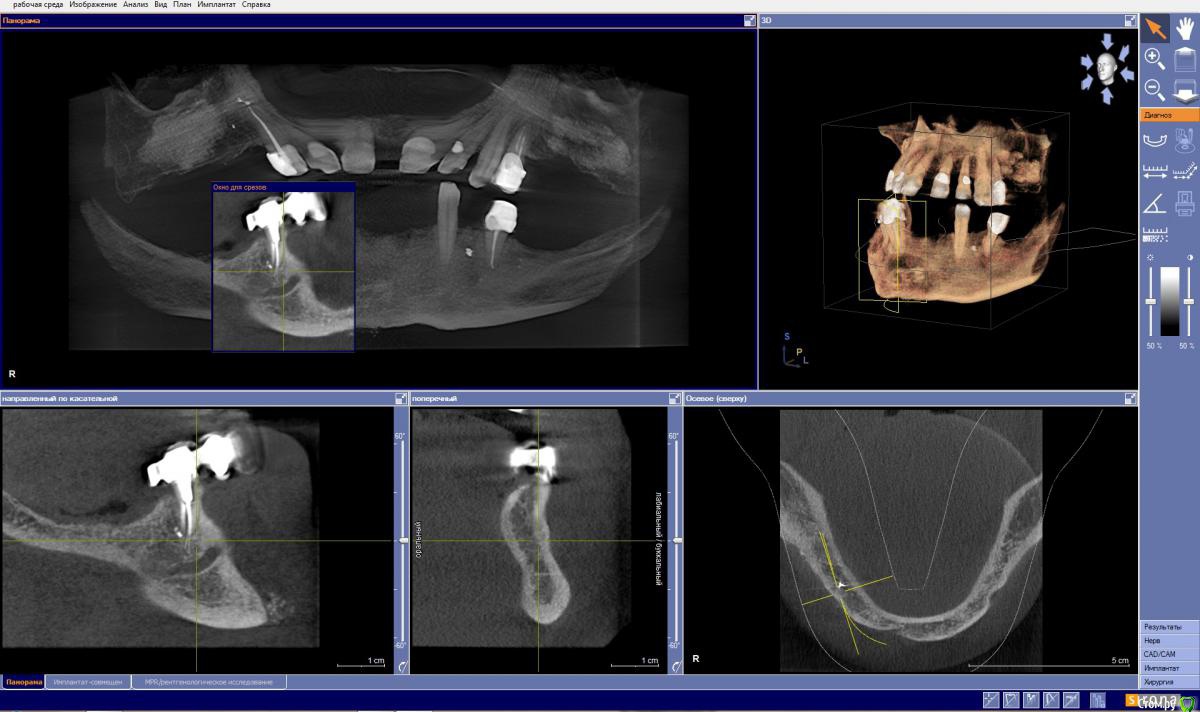

DR.P Опубликовано 1 февраля, 2015 Поделиться Опубликовано 1 февраля, 2015 Низ либо все удалять и делать условносъемный на балке, либо удалять 4.5 и делать бюгель на телескопах с шариковым аттачментом или фрикционным штифтом. Верх мк мост учитывая состояние нижней челюсти - мост. Жевательную группу либо имплантаты или бюгель Ссылка на комментарий

колесников Опубликовано 1 февраля, 2015 Поделиться Опубликовано 1 февраля, 2015 для начала : что хочет пациент? съёмный,несъёмный,что по эстетике предъявляет? носил ли съмные до того? что с внчс? готов ли растаться с оставшимися зубами? когда сделана пластика? он вкурсе что слева она не удалась? теперь к вам. как вы привыкли работать,классика или немедленая нагрузка? знакомы с ,,всё на 4ёх,, или ,,всё на 6ти,,? пластика прикреплёной слизистой или ,,розовая десна,, на протезе? с какими системами предпочитаете работать?исходя из вариантов ответов на эти вопросы можно предлагать варианты плана лечения. на мой взгляд всё удаляется и имплантируется. но этапность , количество имплантов и конечный вид конструкции пока не понятен. 1 Ссылка на комментарий

колесников Опубликовано 1 февраля, 2015 Поделиться Опубликовано 1 февраля, 2015 (изменено) значит отвечу по пунктам. к съемному пациент готов,тк его ориентировали к съемнику на имплантах. съемник носил-видно по замку на премоляре низ справа. срасстаться с зубами готов,но скрипя зубами.работать привык по классике. съемников на имплантах в моей практике было мало. имплантолог у меня опытный,пластику делает. с розовой десной на протезе знаком конечно. системы у нас в клинике Semados и Misкое что прояснилось. я думаю внизу съёмник стоит оставить. пациент привык ,а у нас тут приличное межальвеолярное . делать ли бюгель или съёмный на имплатах-это детали. внимание на верх. фронт хоть и крепкий но имеет место клиническое выдвижение и приличные диастемы. их либо собирать ортодонтически либо распрощаться с ними. меня смущает область синуслифтинга справа. по виду это интегрированый био-ос. это самый плохой вариант интегрированого материала. примерно 1го типа и абсолютно не васкуляризированый. имел неприятный опыт работы с такой костью. интеграции имплантата не произойдёт. что делать? можно попробовать сформировать ложе под имплант и оставить на месяц-полтора,а после установить имплант. либо обойти эту зону. слева ещё хуже-там прорастание эпителия между гранул материала. опять же либо не трогать либо повторная пластика.... короче надо прикинуть на артикуляторе,покрутиь кт. подумать ,посчитать. но всегда остаётся 4 импланта во фронте и балка Изменено 1 февраля, 2015 пользователем колесников 1 Ссылка на комментарий